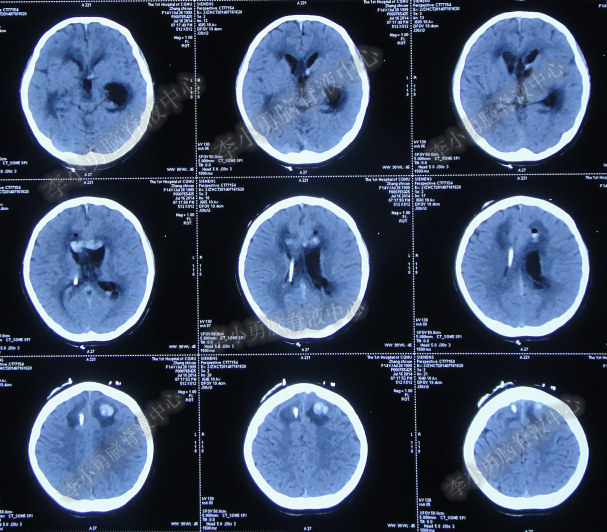

腰大池持续引流20天内,体温仍间断高热,曾3次脑脊液细菌培养均示鲍曼不动杆菌,先后使用利奈唑胺+克倍宁,利奈唑胺+克倍宁+奥硝唑,舒普深+米诺环素+来立信+氟康唑,舒普深+米诺环素+美罗培南+氟康唑,及日达仙、人免疫球蛋白提高免疫力,但颅内感染仍控制不住,期间多次头部CT检查均示脑室无明显扩张(图-7、图-8、图-9)。

图-7:2014年6月9日头部CT

图-8:2014年6月14日头部CT

图-9:2014年6月21日头部CT